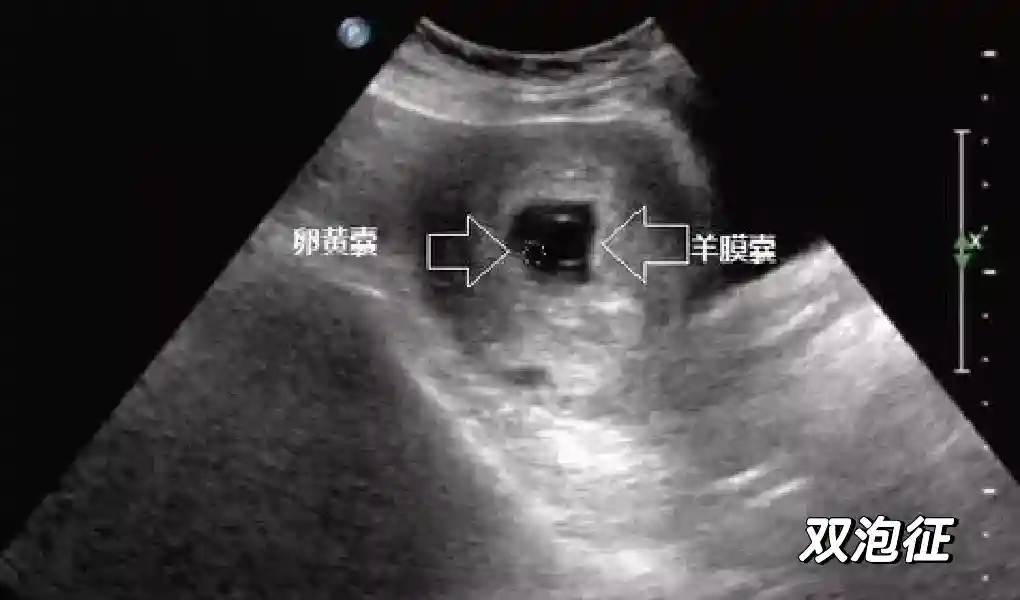

5??羊膜:早孕期羊膜囊菲薄,超聲常不能顯示。孕7周以后加大增益或者用高頻超聲可以顯示羊膜。羊膜囊位于絨毛膜內(nèi),胚胎位于羊膜囊內(nèi)。隨著胚胎增長(zhǎng),羊水增多,羊膜囊增大,孕12-16周時(shí),羊膜與絨毛膜全部融合,胚外體腔消失。宮腔線(xiàn)一側(cè)內(nèi)膜內(nèi)一圓形增強(qiáng)回聲區(qū),中央有小囊狀液性暗區(qū),宮腔線(xiàn)局部突起變形,稱(chēng)蛻膜內(nèi)征,用于判斷早早孕。

5??羊膜:早孕期羊膜囊菲薄,超聲常不能顯示。孕7周以后加大增益或者用高頻超聲可以顯示羊膜。羊膜囊位于絨毛膜內(nèi),胚胎位于羊膜囊內(nèi)。隨著胚胎增長(zhǎng),羊水增多,羊膜囊增大,孕12-16周時(shí),羊膜與絨毛膜全部融合,胚外體腔消失。宮腔線(xiàn)一側(cè)內(nèi)膜內(nèi)一圓形增強(qiáng)回聲區(qū),中央有小囊狀液性暗區(qū),宮腔線(xiàn)局部突起變形,稱(chēng)蛻膜內(nèi)征,用于判斷早早孕。#超聲 #早孕檢查 #妊娠